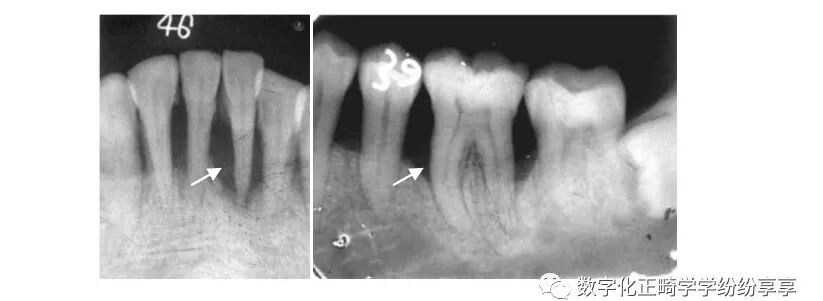

牙槽骨混合型吸收

曲面断层片怎么看正畸【曲面断层片(全景片)】如何解读和查看:牙周?牙体?牙髓?关节?_https://www.jmylbn.com_新闻资讯_第15张

牙槽骨在水平吸收的基础上,同时伴有个别牙或多数牙的牙槽骨垂直吸收。多见于牙周炎晚期。

牙发育异常 Dental anomalies:

畸形中央尖 曲面断层片怎么看正畸【曲面断层片(全景片)】如何解读和查看:牙周?牙体?牙髓?关节?_https://www.jmylbn.com_新闻资讯_第16张

牙内陷

曲面断层片怎么看正畸【曲面断层片(全景片)】如何解读和查看:牙周?牙体?牙髓?关节?_https://www.jmylbn.com_新闻资讯_第17张

①右上 2 畸形舌侧尖(伴阻生牙);②左上 2 畸形舌侧窝;③右上 2 牙中牙